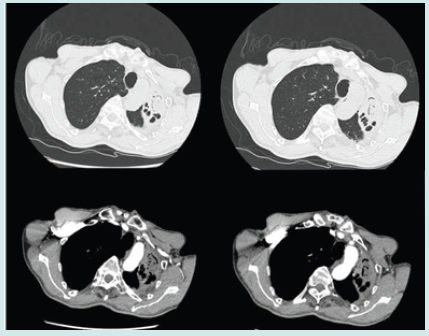

In May 2020, a 63-year-old male patient presented to our outpatient clinic with a cough, expectoration and blood in the sputum with no apparent inducements. He was diagnosed with Aspergillus infection and antifungal treatment was recommended, but he did not use antifungal medication for his own reasons. He underwent closed chest drainage for pneumothorax in 2005, kidney stone surgery in 2015 and rectal polypectomy in 2020. To make matters worse, his cough, expectoration and blood in sputum tended to deteriorate since April 2021. Combined chest CT and bronchoscopic findings suggest CPA (Figure 1). NGS examination of the pathogen of lavage solution suggested Aspergillus fumigatus. Subsequently, he received oral voriconazole antifungal therapy for one month with no significant change in lung lesions and persistent symptoms.

Figure 1: Chest CT showed bronchial dilatation and chronic inflammation in the anterior and posterior segments of the upper lobe of the left lung, with destruction of the left lung. Fibreoptic bronchoscopy showed a patent, twisted left main bronchus with congested mucosa. A large amount of purulent secretions was seen in the right branch of the left upper lobe.